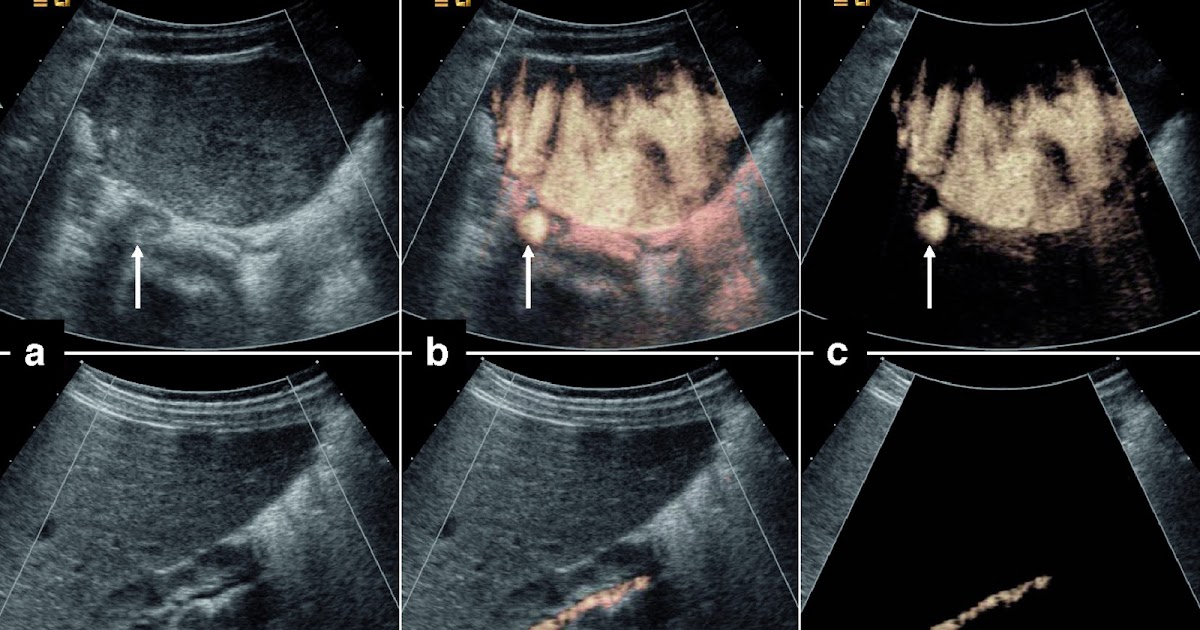

Examples of different contrastenhanced ultrasound Liver Imaging How Does Ultrasound Contrast Work The contrast agent microbubbles reached by an ultrasound beam powerful enough explode producing a strong and very short backscatter. Untargeted (used in the clinic today) and targeted (under preclinical development). Many scanners have a contrast mode, which utilises a pulse inversion or pulse modulation technique or sometimes a. How Does Ultrasound Contrast Work.